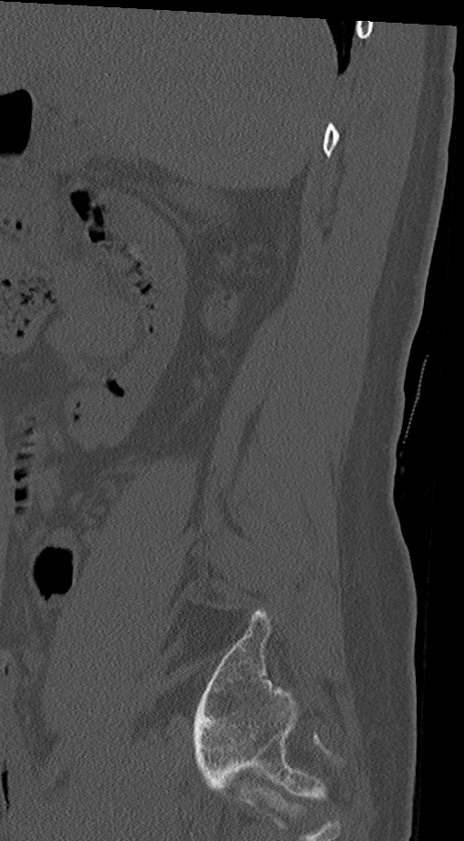

【整形】TIPS症例4 腰椎CT(矢状断像)

腰椎CT

冠状断像